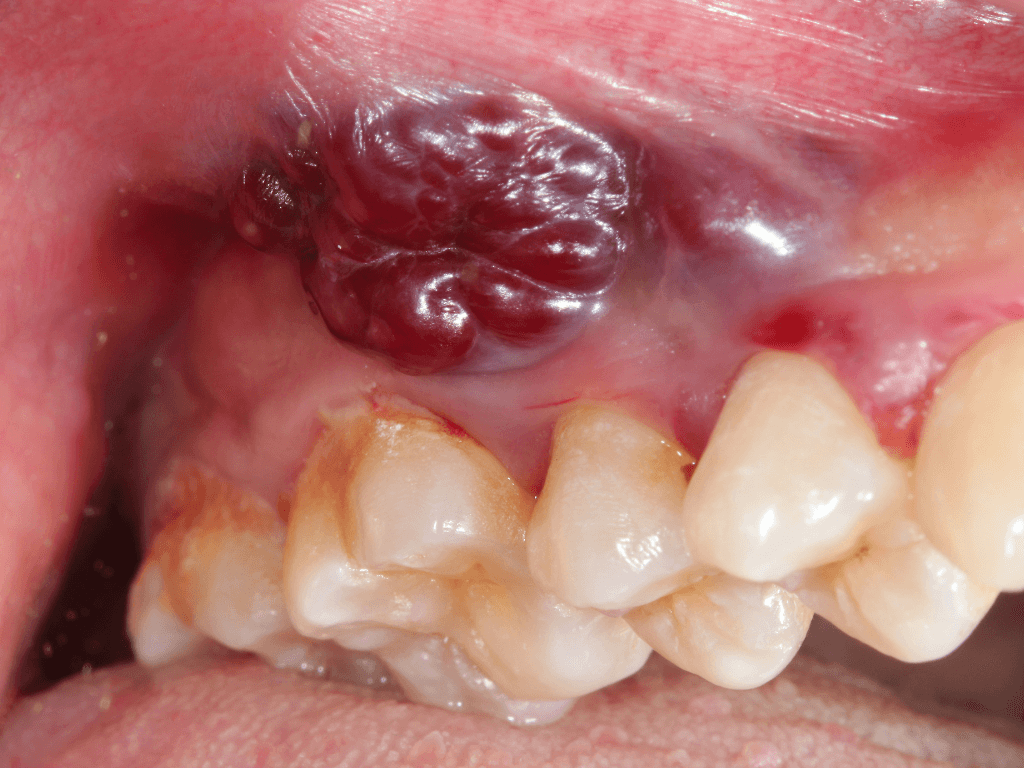

Oral cancer

Oral cancer is a malignant (cancerous) growth that develops in the tissues of the mouth or oralmrs-core